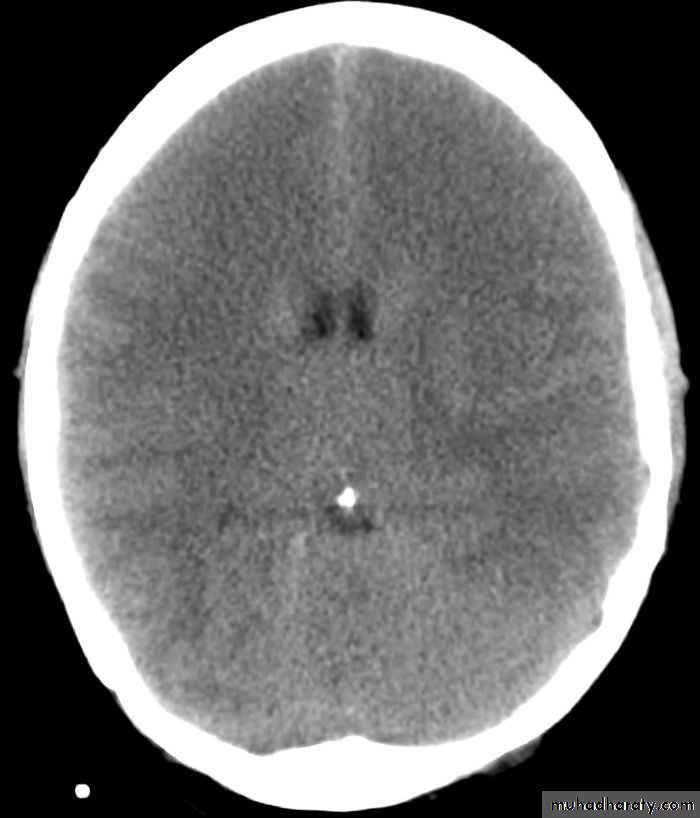

C-Intracranial hemmorhage (I.C.H.)

I.C.H.

2-CT-Scan

3-MRI